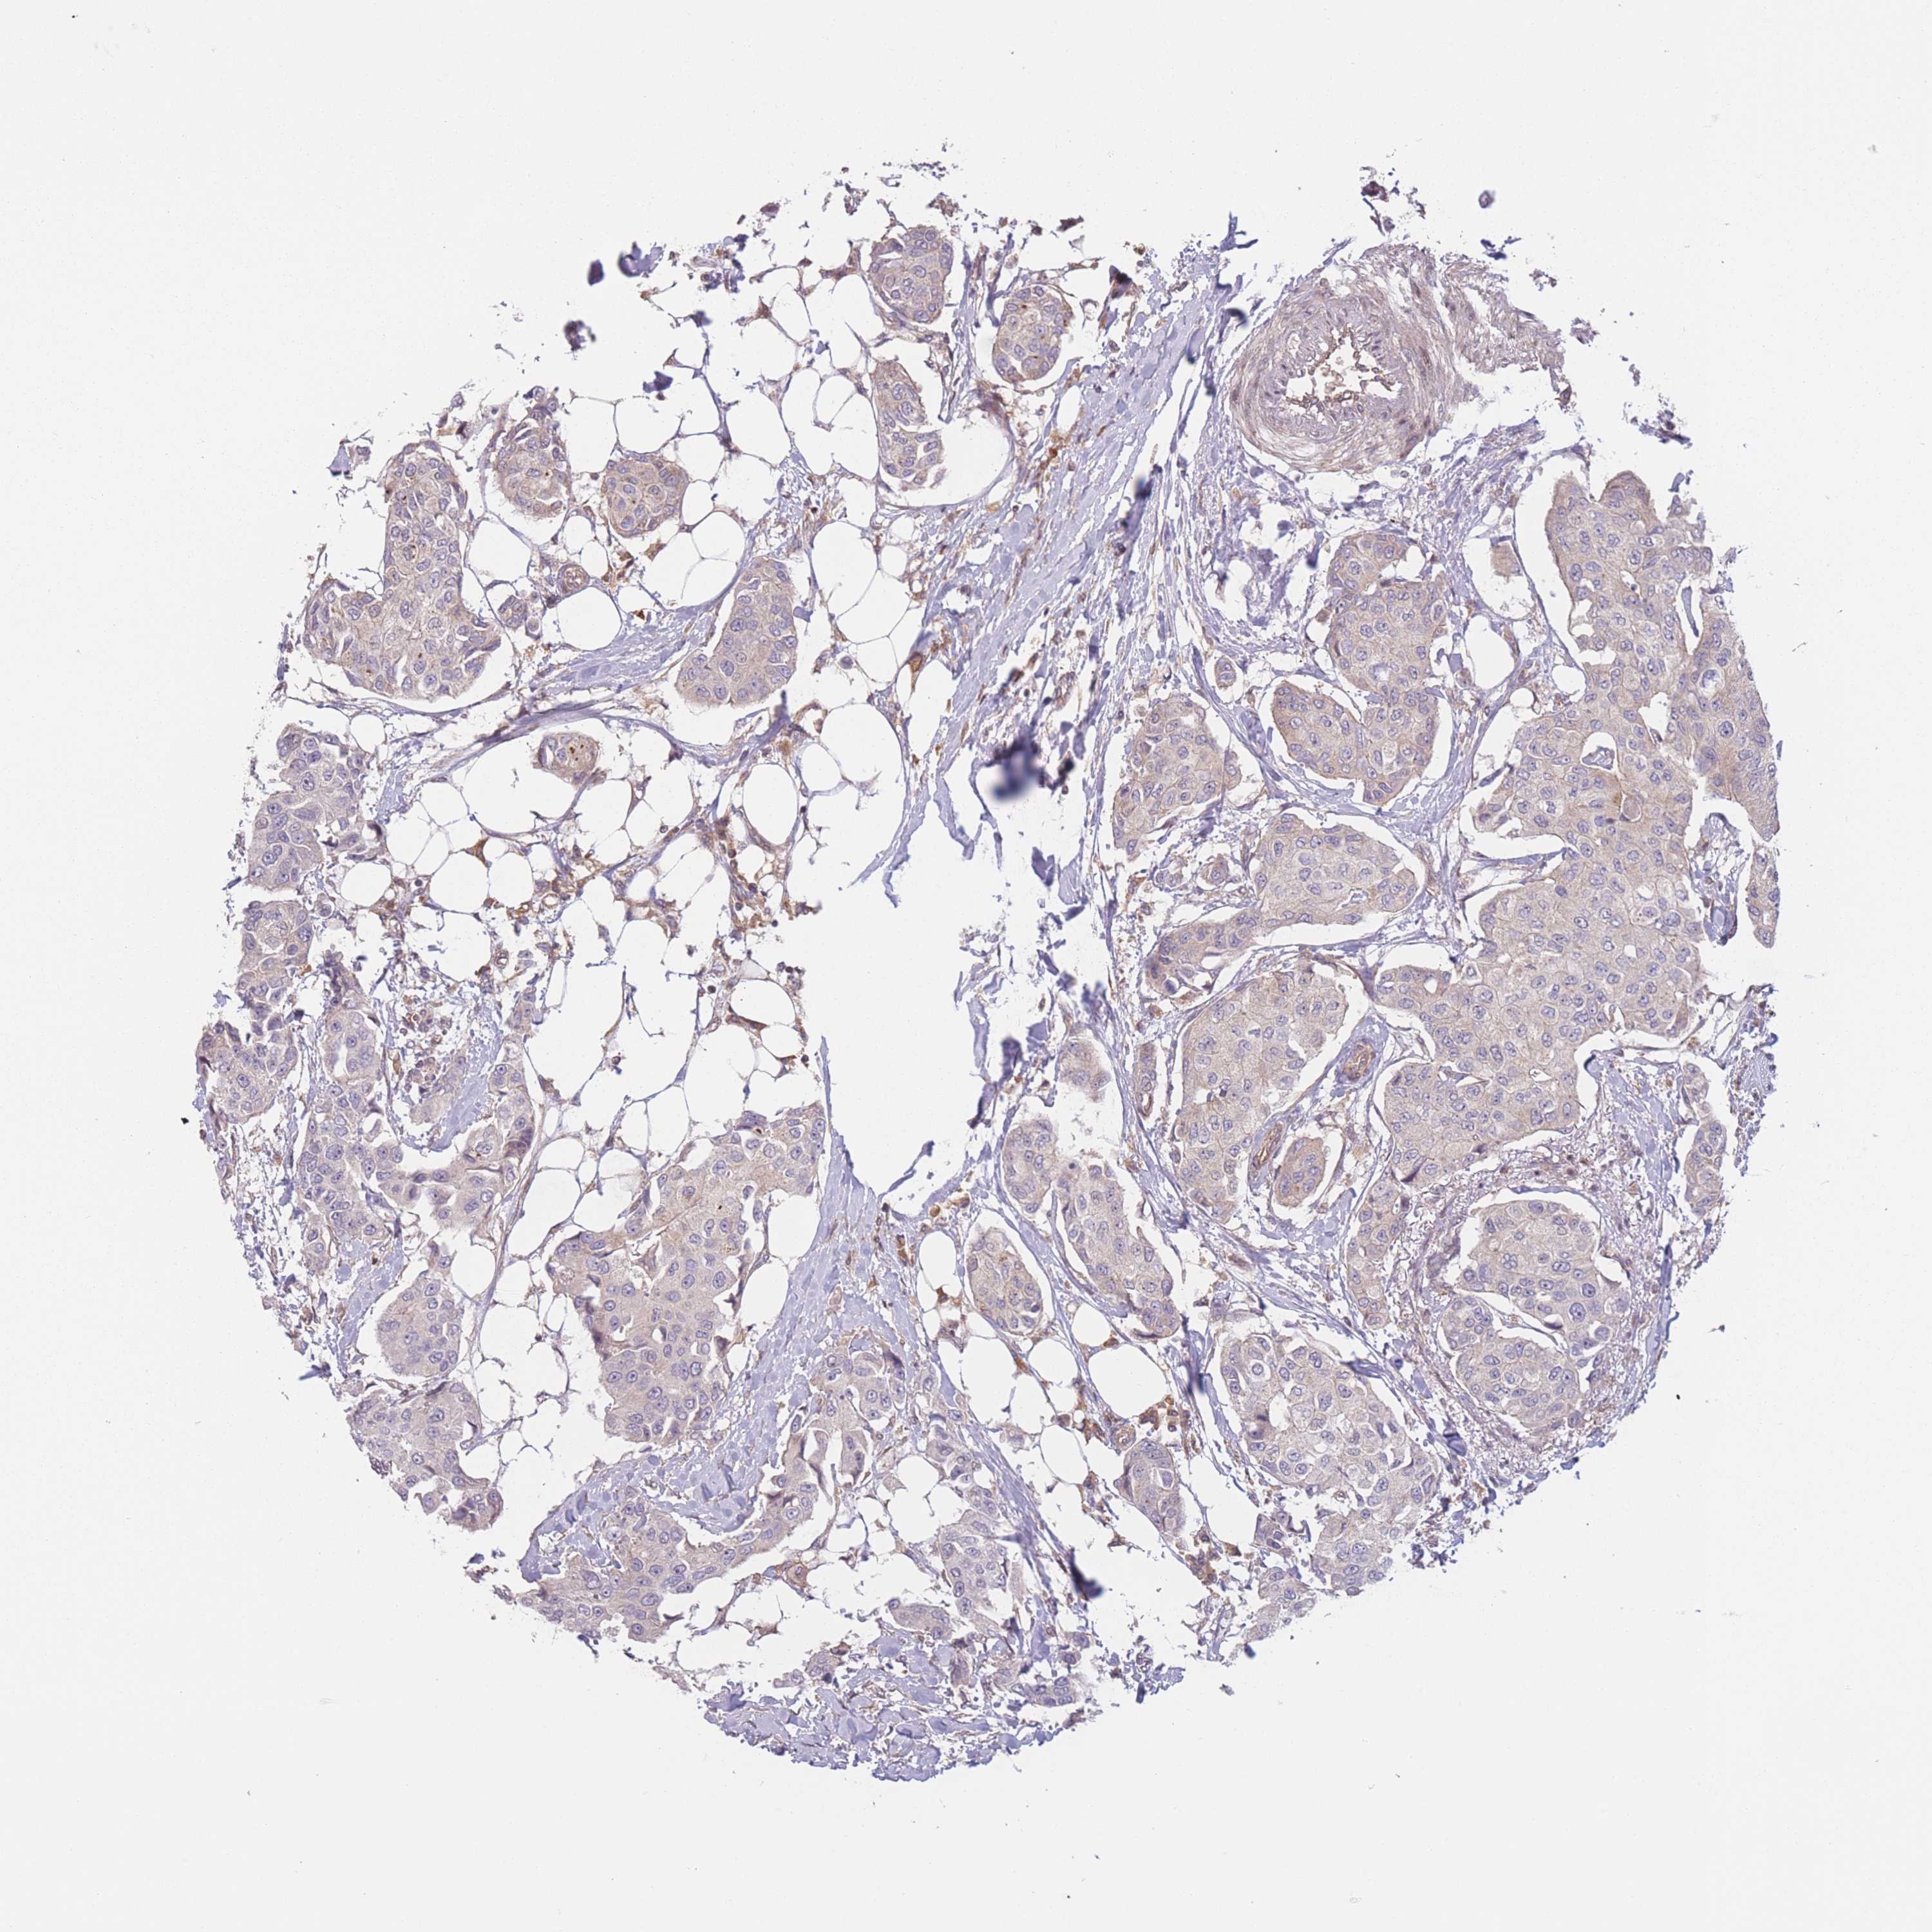

CANCER BREAST CANCER Show tissue menu

BRCA TCGA BRCA VALIDATION PROTEIN EXPRESSION